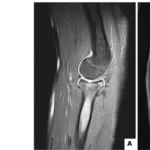

膝蓋骨垂直骨折の患者

一昨日, 自転車乗車中にクルマに接触されて転倒して, 膝蓋骨骨折を受傷した超高齢患者さんが紹介で受診されました.

引用元:Cramer KE. Patellar fractures: Contemporary approach to treatment. J Am Acad Orthop Surg. 1997. 5.

持参されたX線・CTを確認したところ, 骨折線は縦方向の垂直骨折(Vertical fracture)でした.

骨折部の段差(step-off)が2-3 mm以上, ズレ(displacement)が1-4 mm以上の場合は, 手術が実施されます.

垂直骨折(Vertical)の場合は, ネジ(Screws)固定が選択されます.

上記以外は, 装具(Brace)を装着して, 安静を保ちます.

引用元:Steinmetz S. Practical guidelines for the treatment of patellar fractures in adults. Swiss Med Wkly. 2020. 150.

膝蓋骨の治療方針は, 治療方針は骨折部のズレ(displacement)や段差(step-off)で決定されます.

- 段差 2–3 mm以上

- ズレ 1–4 mm以上

なら手術が必要となり, 垂直骨折の場合はネジ(スクリュー)での固定 が選択されます.

紹介の患者さんは, ズレはほとんどなく, 手術不要. 膝関節を伸展位で固定する装具治療とし, 自然治癒を待つことにしました。